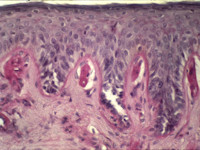

Histologisch onderzoek van een bullae bij PCT laat een subepidermale cel-arme blaar zien met karakteristieke festoning van de dermale papillen. Directie IF microscopie laten vaak immunoglobulinen (hoofdzakelijk IgG, minder vaak IGM), complement en fibrinogeen ter plaatse van de dermale-epiderdale overgang en rond bloedvaten van de papillaire dermis.

Erythropoietische protoporfyrie Histologie (immunofluorescentie) porphyria cutanea tarda

PAS positieve deposities IgG rond vaten

PA-Foto: M Lecha, H Puy, JC Deybach - Wikimedia (Creative Commons License 2.0).

IF-Foto: www.dermatlas.net.